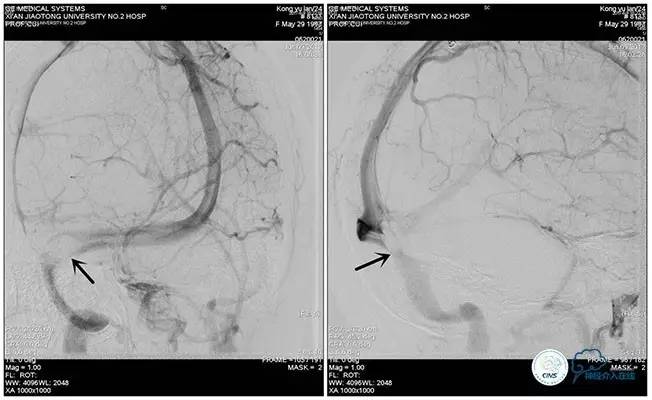

术中右侧ICA造影

右侧ICA斜位及窦内造影

右侧ICA斜位

窦内造影及路图

术中测压:

远端:520mmH2O,

近端:190mmH2O。

治疗方案:

1、8mm×40mm , EverCross球囊扩张;

2、8mm×40mm,Protégé自膨支架成形术。

术后右侧ICA造影

术后远、近端压力差为:0

术后右侧ICA斜位